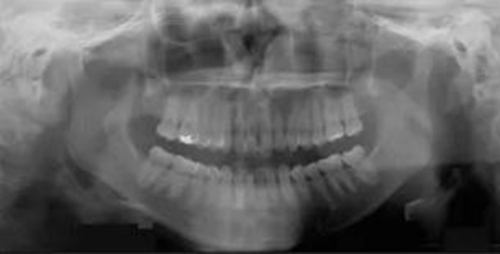

3.測量分析:治療前記錄提示該患者左右磨牙與尖牙為安氏II類關(guān)系,上頜牙弓重度擁擠,下頜牙弓輕度擁擠,深Spee曲線。6.3mm深覆蓋,80%深覆合。牙齒無齲,無第三磨牙。

頭側(cè)分析提示為骨性安氏II類(ANB,8.4°;Wits,3.6mm),高角(SN-MP,44.9°),上頜切牙略舌傾(U1-SN,96.2°),下頜切牙略舌傾(IMPA,88。3°)(圖2;表)

治療后全景片提示間隙得到關(guān)閉,除了左下頜第一前磨牙外牙根平行度可,無明顯骨及牙根吸收。(圖7)